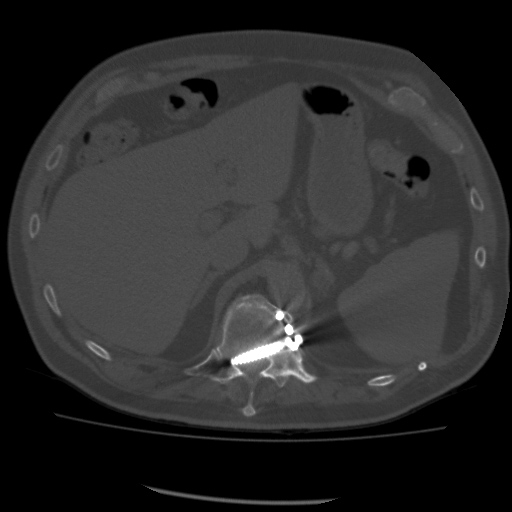

|

| 70 year-old man with history of L1 and L3 injury and T11-L3 spinal fusion in the 1990's. Recent worsening of chronic lower back pain. Standard radiographs (left two images) show a vertebral body corpectomy cage at T12-L3 with placement of a left lateral side plate at the same levels. There are two proximal screws at T12, one of which enters the spinal canal as shown on subsequent CT (right two images). There are two distal screws at L3, the most distal of which enters the L3-4 disk space (lateral radiograph). |